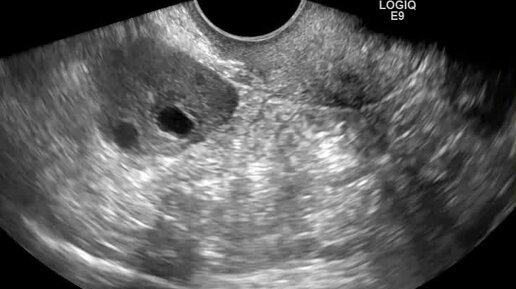

Поперечное сканирование матки. Свободное смещение правого яичника

Ультразвуковые находки от врача УЗД Зорина Я.П.